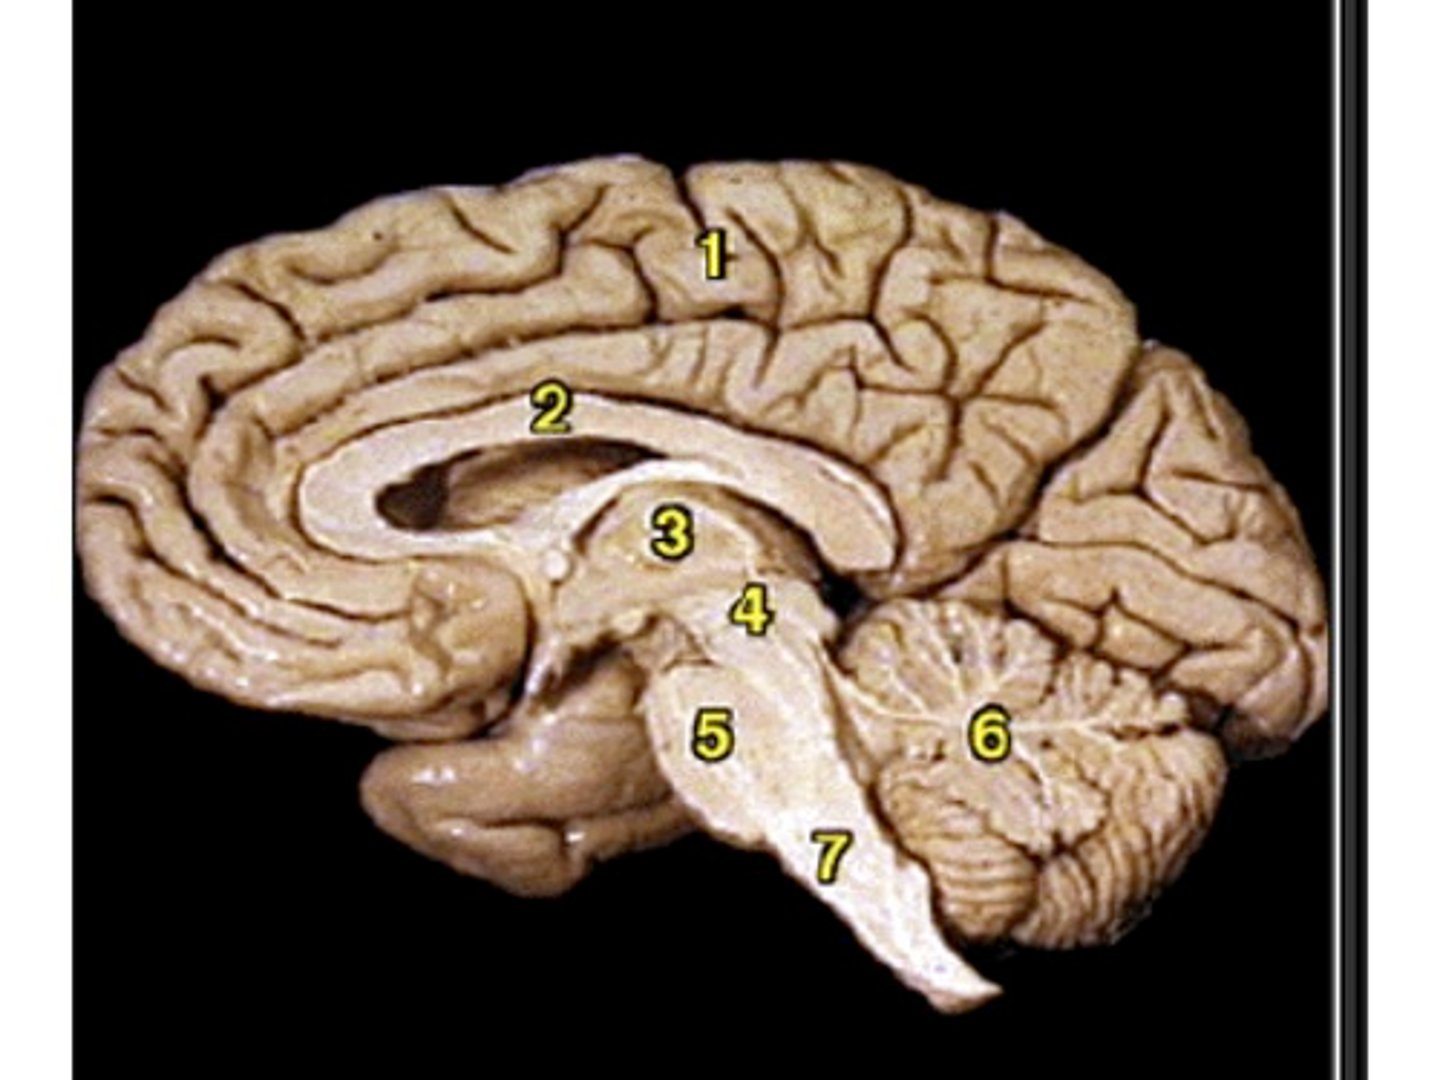

Sagittal View